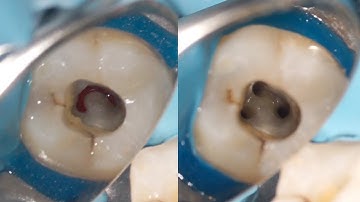

Access Opening in Mandibular Second Molar with Distal Caries